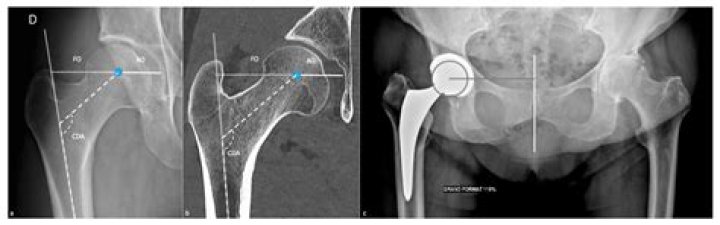

The hip joint (see the image below) is a ball-and-socket synovial joint: the ball is the femoral head, and the socket is the acetabulum. The hip joint is the articulation of the pelvis with the femur, which connects the axial skeleton with the lower extremity.

How big is a femoral head?

The natural size of the femoral head usually ranges from 40 to 54 mm, with smaller sizes usually found in females. In the initial development of hip arthroplasty, artificial femoral heads were designed to replicate these anatomical dimensions.